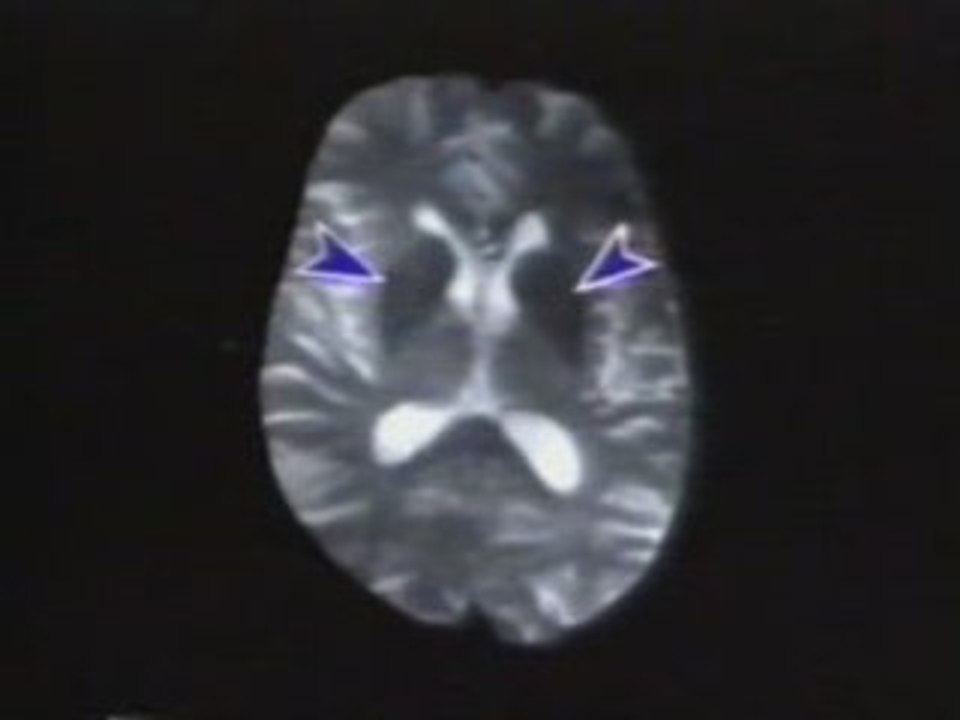

¿Cuánto tiempo dura el período de pérdida de células neuronales cuando se está enfermo de Parkinson? ¿Qué factores aceleran la pérdida de neuronas en la enfermedad de Parkinson? <br /><br />Consulte a su Médico.<br /><br />De la mano de un médico, te daremos a conocer información muy interesante. De las dudas que normalmente tenemos, te daremos a conocer respuestas directamente de expertos en el tema.